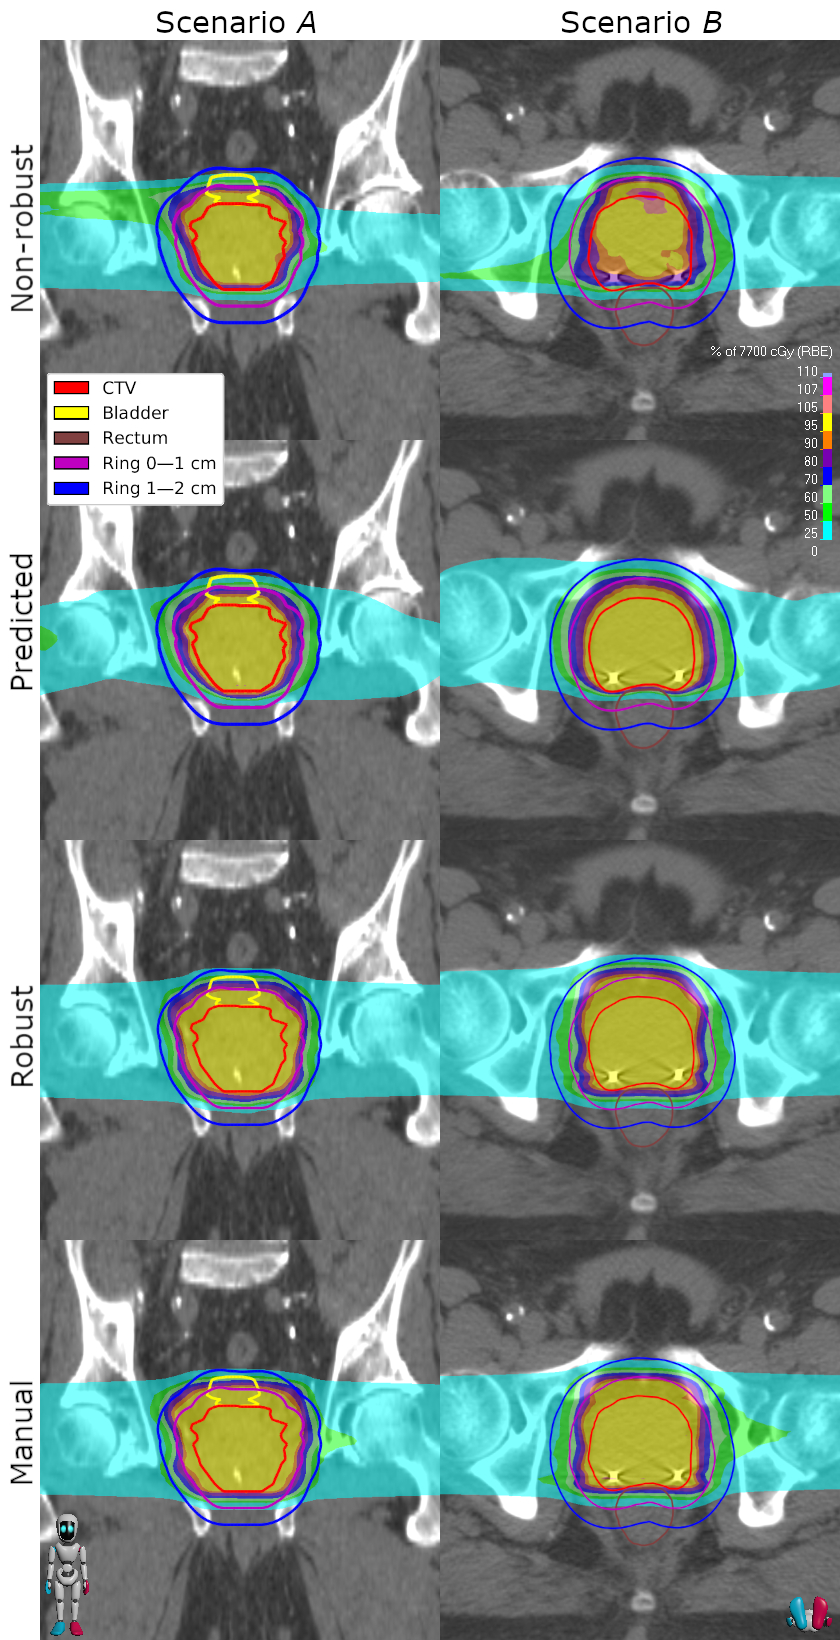

Figure 4: Two different scenarios with the non-robust (first row), the predicted (second row), the robust (third row), and the manual (fourth row) doses. The left column shows a coronal slice of scenario A𝐴A where the patient has been translated down 0.5cm0.5cm0.5\;\mathrm{cm} with respect to the image. The right column shows a transversal slice of scenario B𝐵B where the patient has been translated down 0.5cm0.5cm0.5\;\mathrm{cm} with respect to the image and a density shift of +3%percent3+3\;\% has been applied.

To verify the feasibility of the proposed pipeline, we perform a qualitative analysis for one test patient and a quantitative analysis based on the entire test dataset. In Figure 4, two scenarios for a test patient are visualized. The non-robust ground truth dose fails to give a sufficient target coverage—in particular, in the transversal view, one can see that large parts of the CTV receive less than 95%percent9595\;\% of the prescribed dose. However, the scenario dose prediction model has been trained to predict doses with a better target coverage, and we see indeed that the predicted dose successfully covers the CTV in these scenarios. Finally, the automatically generated robust deliverable dose is generated by performing a robust dose mimicking using all the predicted scenario doses as reference doses and is expected to ensure coverage of the CTV in most or all of the scenarios. For the two scenarios displayed, the CTVs are well-covered, whereas the dose decays slower beyond the CTV outline than the corresponding predicted scenario doses—this is due to the robust plan needing to account for the outcome in all scenarios. The manually generated benchmark has similar target coverage and decay around the CTV compared to the automatically generated dose, but slightly more dose spillage in the area beyond 2 cm from the CTV.

Furthermore, the DVHs corresponding to the scenarios in Figure 4 are displayed in Figure 5. The DVHs of the predicted scenario doses are relatively similar to those of the non-robust dose in all ROIs except for the CTV, where the target coverage is instead more similar to that of the prescribed dose. This is what we wanted to achieve with our scenario dose prediction since the spatial component of the loss function used to train the scenario model is expected to make the predicted doses similar to the ground truth scenario doses, while the DVH component is aimed at maintaining the target coverage of the nominal dose. We can also see that the automatically generated robust dose has a similar target coverage as the predicted dose in both scenarios, meaning that the target coverage of the predicted doses successfully propagates to the robust dose—however, naturally, this comes with the cost of a slight increase in dosage to the rectum, bladder and the target surroundings. The automatically generated robust dose has similar DVHs compared to those of the manual benchmark.